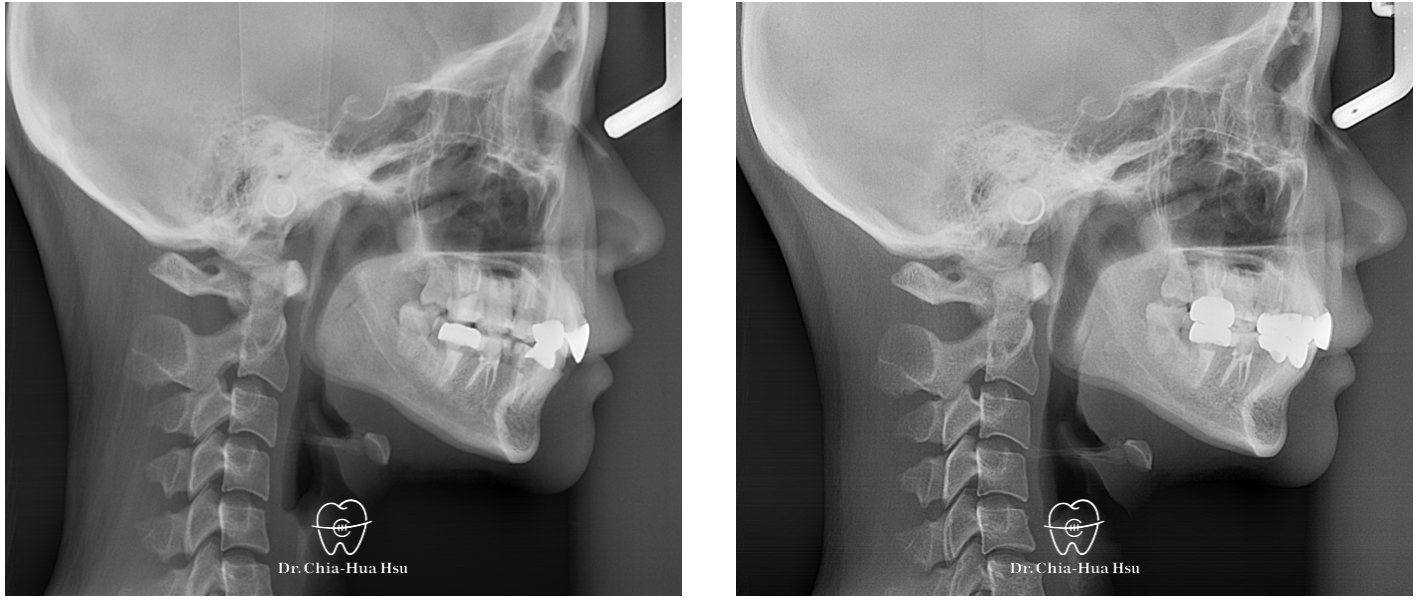

- 這位年輕女性在別間診所第一次隱形矯正完後咬合變成深咬的狀態,患者自述矯正後顳顎關節開始不舒服,後續接受咬合板治療等到症狀比較穩定後,我們才開始進行再次矯正的療程。

- 問題分析:患者是骨骼一類咬合(Skeletal Class I)伴隨深咬。

- 治療方式:使用傳統金屬矯正器,搭配骨釘、骨板,整平下顎咬合平面,改善深咬。另外,上顎門牙貼片也有稍作調整,恢復適當的長寬比例。

- 治療結果:深咬改善,患者也明顯感受關節與咬合更舒服。

治療前

治療後